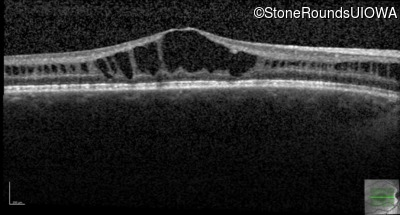

Optical Coherence Tomography - Left - 20/50

Exemplar / OCT Stack

OCT Stack